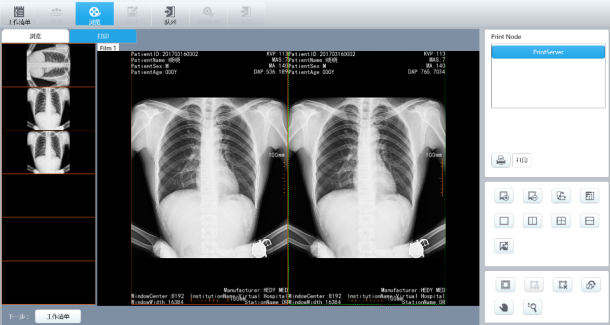

三:一体化智能图像采集处理工作站

1、全中文图形化菜单,集登记、摄影**、图像处理及传输、报告打印、胶片打印等功能于一身,集成度高,操作方便。操作得心应手、三维模拟示教系统初学者轻松上手。

2.专业的图像处理软件

u 图像回访:缩略图显示,序列回放工具,数字减影回放;

u 图像处理:窗宽/窗位调整,箭头、文字等标注,角度、距离测量,图像缩放、平移、左右翻转、上下翻转、旋转,黑白反转,减影蒙片选择;

u 图像存储:图像实时存储,DICOM图像发送,光盘刻录,导出存储(可选用多种存储格式:Bitmap,JPEG,AVI等直接用于Word及Powerpoint等办公软件,方便医生诊断报告和论文的书写;

u DICOM 3.0:**兼容各品牌激光相机、PACS系统;

u 病历管理:数据库管理,图文报告,支持WORKLIST。